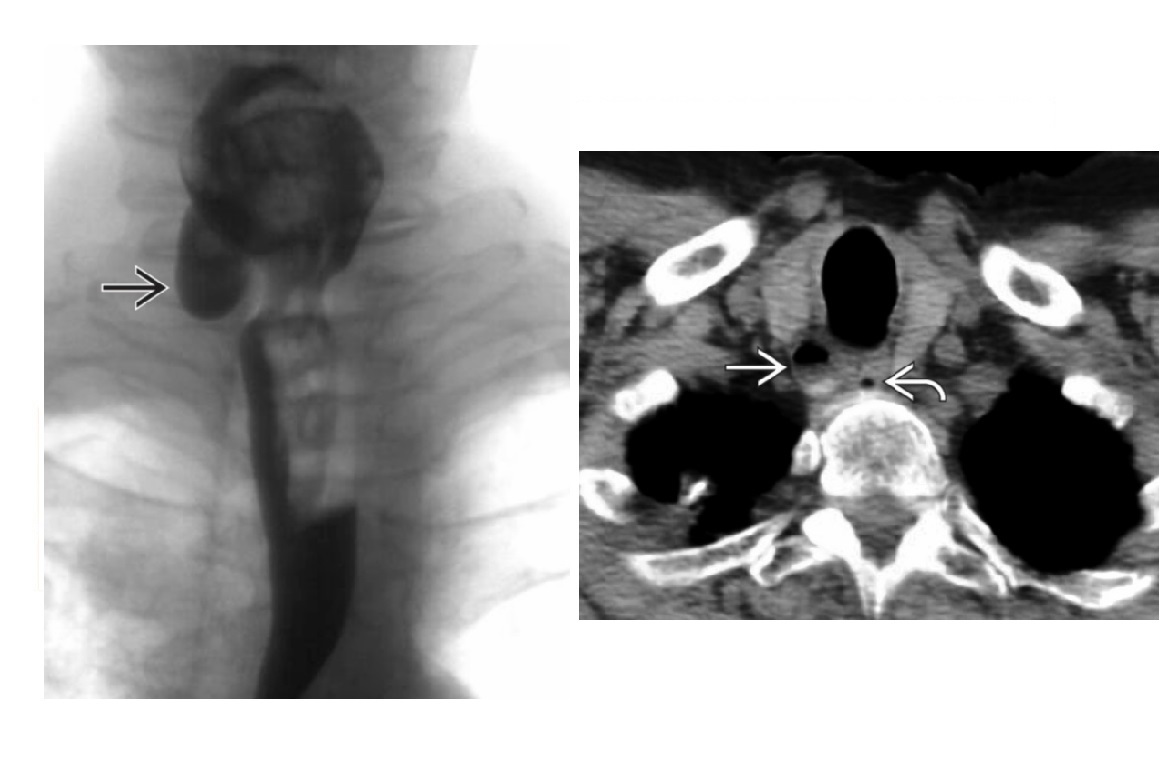

Zenker Diverticulum

Outpouching with rounded contour posteriorly in the neck is above the cricopharyngeus muscle

In hypopharynx!!!

Site of weakness is the Killian dehiscence - between the inferior pharyngeal constrictor muscle and cricopharyngeal muscle

Traction diverticulum

Dysphagia in elderly person. Previous TB.

Barium-filled tented or triangular outpouching in the mid oesophagus

Acquired condition due to subcarinal or perihilar granulomatous lymph node pathology (TB, histo)

External force on oesophageal wall, such as mediastinal inflammation, that adheres and pulls on oesophageal wall

Killian - Jamieson Diverticulum

Small outpouching in the cervical oesophagus. Anterior and lateral direction